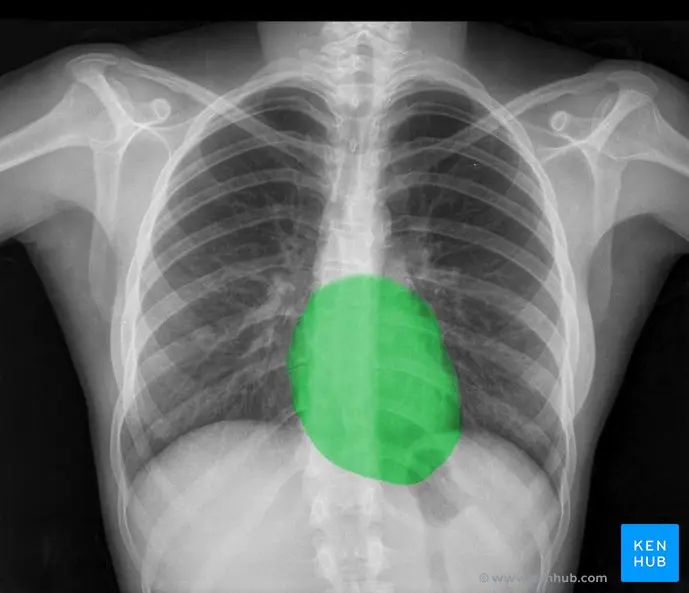

Imagen de Pulmones Sanos en Radiografía

Una radiografía de tórax de un individuo sano mostrará pulmones con una textura homogénea y oscura, indicando la presencia de aire. Los vasos sanguíneos pulmonares pueden ser visibles como líneas finas y ramificadas. El corazón y los grandes vasos se observarán en su tamaño y forma normales. La evaluación de una radiografía de tórax requiere la consideración de la proyección (PA, AP o lateral), la posición del paciente y la calidad técnica de la imagen. Las variaciones en la apariencia de los pulmones pueden depender de factores como la edad, la constitución física y el grado de inspiración durante la toma de la imagen.